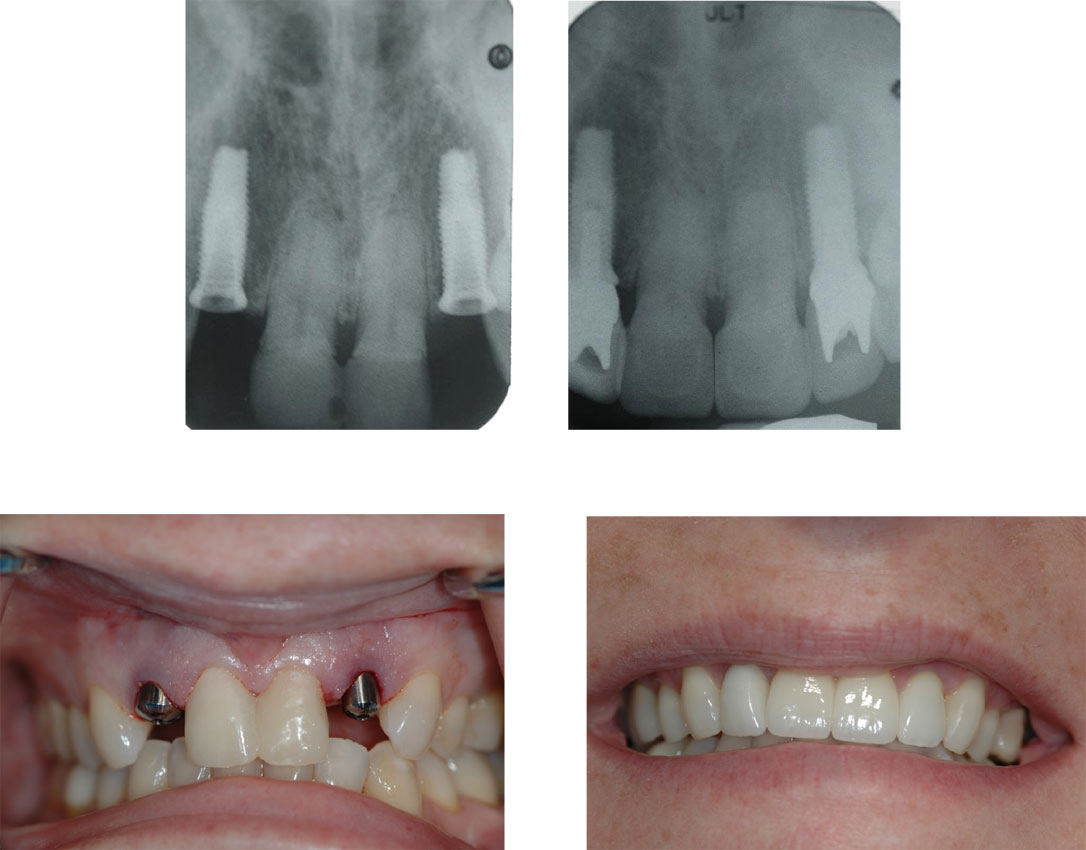

![]() |

| Cấy ghép răng implant có tốt không? |